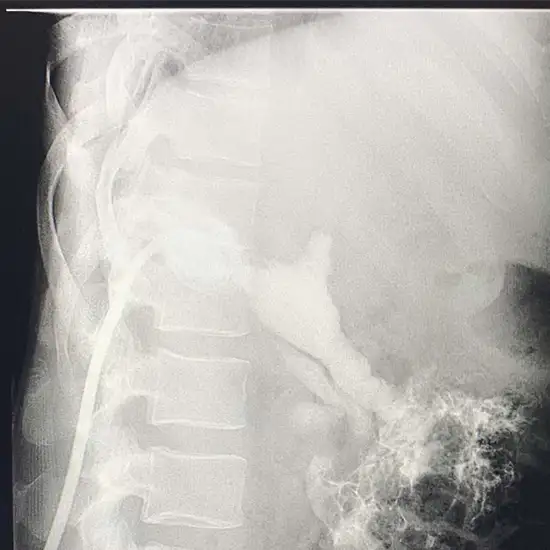

X-Ray Sinogram

A fistula/sinus is an aberrant passage in the body that can be seen using a sinogram/fistulogram. As a rule, a fistula is a malformed tube connecting two organs, while a sinus is a malformed tract or cavity.

A fistulogram can detect fistulas in the anal canal, skin around the anus, vagina, colon, rectum, small intestine, or bladder. A sinogram can assist in diagnosing abnormalities like apparent fluid leakage from the skin or abscess formation.